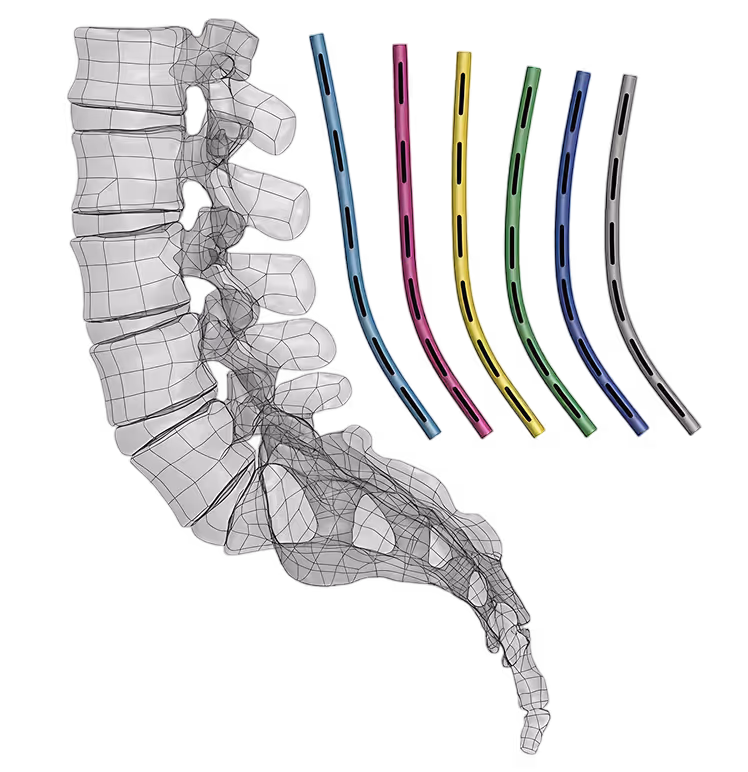

PI-Rod SEGLIGN™

Precision Segmental Alignment Technology

A thoughtfully engineered system of 6 pre-contoured rods matched to patient pelvic incidence (PI) categories. Each rod shape reflects segmental lordosis distributions derived from successful fusion outcome data, helping surgeons select the appropriate rod geometry for their patient's PI category.

6 Rod Configurations.

One Measurement

Lordotic rod profiles derived from asymptomatic subjects and successful fusion outcome data with segmental lordosis targets per level and pelvic incidence.

6 curved rod shapes with level-specific segmental lordosis distributions matched to patient Pelvic Incidence

Lumbar L1-S1 rods and short segment rods that are OR ready